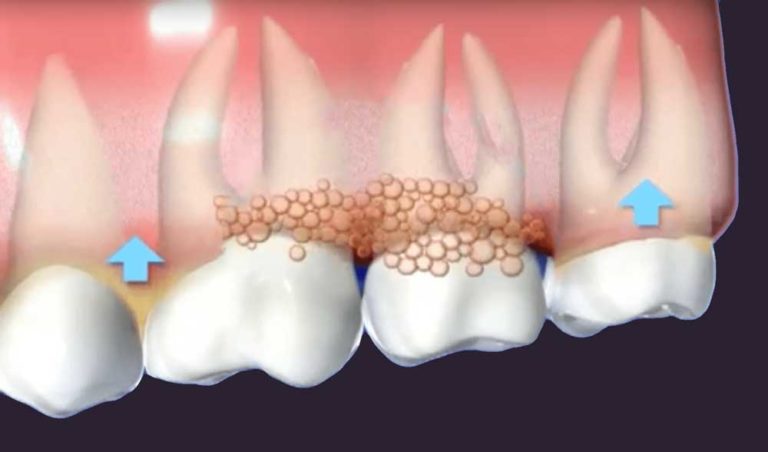

Have you been noticing your gums bleed easily whenever you brush or floss? Or they are starting to pull away from your teeth? These are

Laser Gum Surgery has major health benefits in Wayne, NJ because it improves your oral health by removing bacteria within your mouth that can be detrimental